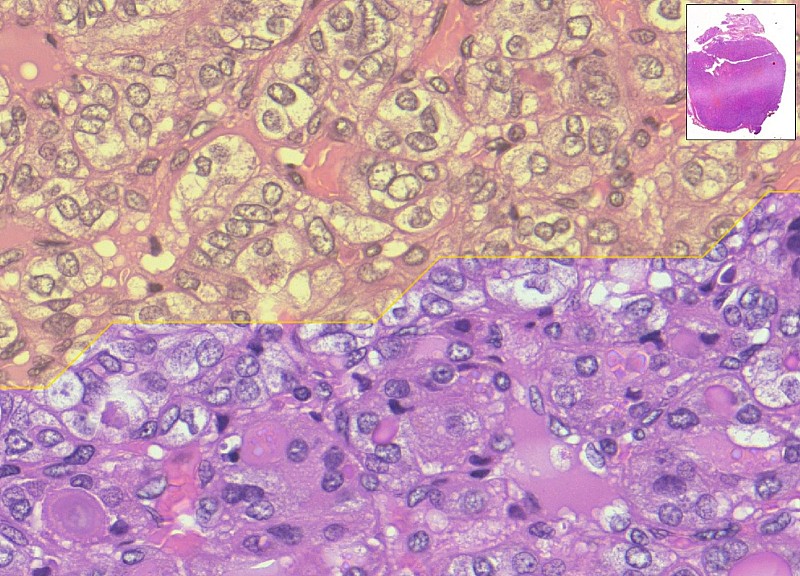

Basato su reti neurali profonde, MiThyCA è stato addestrato su migliaia di immagini ad altissima risoluzione ottenute dalla digitalizzazione dei vetrini istologici. Il sistema è in grado di analizzare campioni complessi in pochi minuti, individuando automaticamente aree e marcatori sospetti che meritano l’attenzione dello specialista.

La sua caratteristica distintiva è il cosiddetto “doppio occhio”: due reti neurali che operano in sequenza. La prima analizza i dettagli cellulari, la seconda restituisce una visione d’insieme del campione. L’integrazione delle due letture consente di segnalare le zone più rilevanti, senza mai sostituirsi al giudizio del medico.

Nei test condotti su casi di carcinoma tiroideo, MiThyCA ha raggiunto livelli di accuratezza paragonabili a quelli di team di professionisti esperti, offrendo un secondo parere oggettivo e riproducibile. In prospettiva, la digitalizzazione dei vetrini potrebbe ridurre i tempi di attesa e favorire l’avvio più rapido di terapie personalizzate.